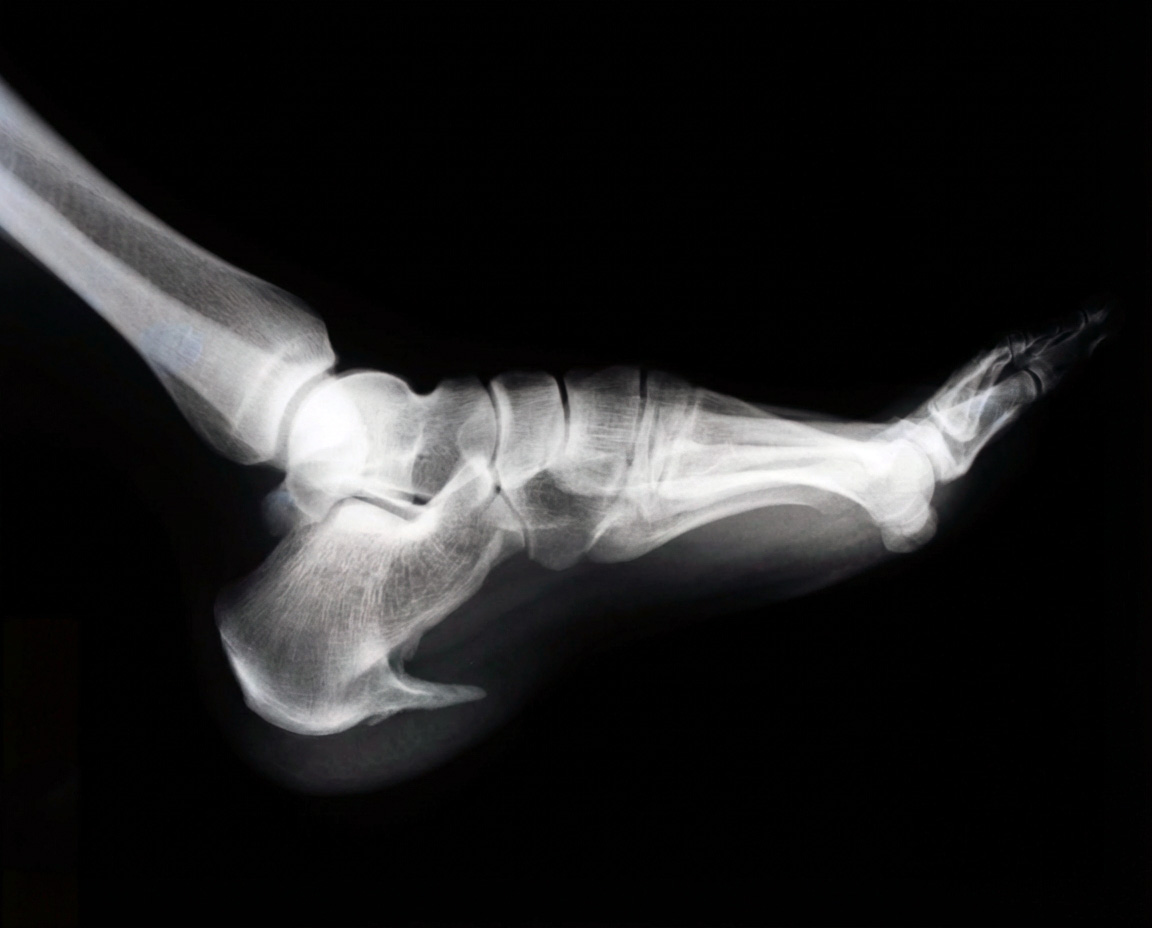

A heel spur is a small, bony bump that grows on the underside of your heel bone (calcaneus), right where the plantar fascia attaches. It forms when calcium builds up over time from ongoing stress or inflammation pulling on that spot. More importantly, most heel spurs don’t actually hurt. Plenty of people have them show up on X-rays without ever feeling a twinge. The pain usually comes from the irritated tissue around it, not the spur itself.

Accurate diagnosis is key to distinguishing between heel spurs and plantar fasciitis, as treatment differs depending on the underlying issue. At The Foot Practice, diagnosis starts with a thorough clinical assessment, including a medical history examination, gait observation, and palpation of the heel. Imaging, such as X-rays, may also be used to rule out other causes of heel pain, such as a broken heel.